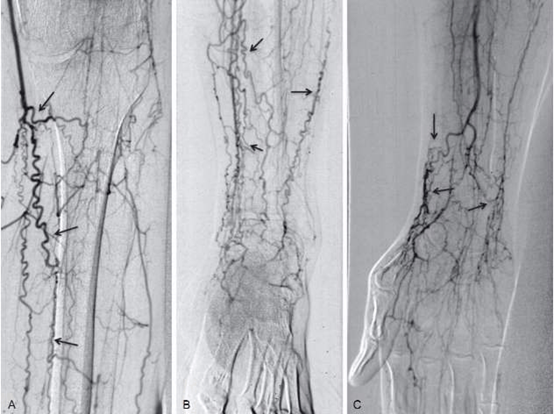

近期,哈醫(yī)大四院血管外科利用準分子激光斑塊消蝕聯(lián)合藥物涂層球囊技術,成功為一例年輕血栓閉塞性脈管炎患者開通閉塞動脈,挽救肢體。患者李某今年32歲,半年前自覺右下肢麻木伴疼痛,一個月前麻涼痛癥狀加重,并逐漸出現(xiàn)了右足跟潰爛發(fā)黑的癥狀?;颊呒凹覍僮咴L了省內(nèi)多家醫(yī)院,醫(yī)生給出了相同的建議:截肢?;颊呒捌淠赣H難以接受余生在輪椅上度過的現(xiàn)實,經(jīng)多方打聽來到哈醫(yī)大四院血管外科就診。黃任平主任經(jīng)過仔細詢問病史,查體,閱讀影像資料后,考慮患者患有血栓閉塞性脈管炎。對于脈管炎的患者并伴有足破潰,如不及時治療,患者截肢幾率非常大。傳統(tǒng)經(jīng)皮動脈球囊擴張成形術(PTA)難以解決長段、閉塞性、炎性增生病變,施行PTA后容易出現(xiàn)血管壁彈性回縮、殘余管腔重度狹窄等。支架的植入也會出現(xiàn)術后急性閉塞和再狹窄發(fā)生,跨關節(jié)病變支架植入術后極易出現(xiàn)支架扭曲、斷裂等現(xiàn)象。正逢哈醫(yī)大四院血管外科引進我省第一臺用于治療下肢血管病變的準分子激光設備,是目前國內(nèi)外十分推崇的腔內(nèi)減容技術。黃任平主任決定用這臺新設備為年輕小伙手術治療,術中黃任平主任首先用準分子激光開通閉塞的血管,然后應用載藥球囊對病變部位進行擴張,手術順利結束。術后下肢動脈血流即刻恢復,目前患者恢復良好,右下肢疼痛涼麻癥狀消失,潰爛部位逐漸好轉。此次哈醫(yī)大四院血管外科采用的準分子激光斑塊消蝕技術在國外已經(jīng)有20多年的應用歷史,技術已然成熟,但在我國起步較晚,在我省尚屬首次應用。它主要通過三種方式來發(fā)揮作用:一是光消蝕作用,主要把物質分子裂解;二是聲壓波效應,主要作用于較硬的動脈硬化斑塊,將其震碎;三是空泡效應,主要是將這些斑塊碎屑組織粉碎成比紅細胞還小的納米級別,因而不會對遠端血管造成栓塞。而且,激光減容技術相對斑塊旋切等其它減容技術,對血管壁的損傷更小。黃任平醫(yī)學博士、博士后,碩士生導師哈爾濱醫(yī)科大學附屬第四醫(yī)院血管外科主任??專業(yè)方向:擅長血管外科的常見病多發(fā)病的診治,從事微創(chuàng)血管病治療與創(chuàng)面治療10余年,治愈各種靜脈曲張、糖尿病足、下肢靜脈血栓、脈管炎、動脈硬化閉塞癥、胸腹主動脈瘤、動脈栓塞、肺栓塞、鎖骨下動脈閉塞、腎動脈狹窄、嬰幼兒血管瘤、血管畸形等近20000例。血管外科門診出診醫(yī)生一覽表出診醫(yī)生出診時間黃任平周一、周二上午8:00-11:30李佳樂周一、周二下午13:00-16:30謝春楊周三、周四上午8:00-11:30馬文超周五上午8:00-11:30出診地點:哈爾濱醫(yī)科大學附屬第四醫(yī)院門診三樓C區(qū)外科3診室咨詢電話:0451-82576869